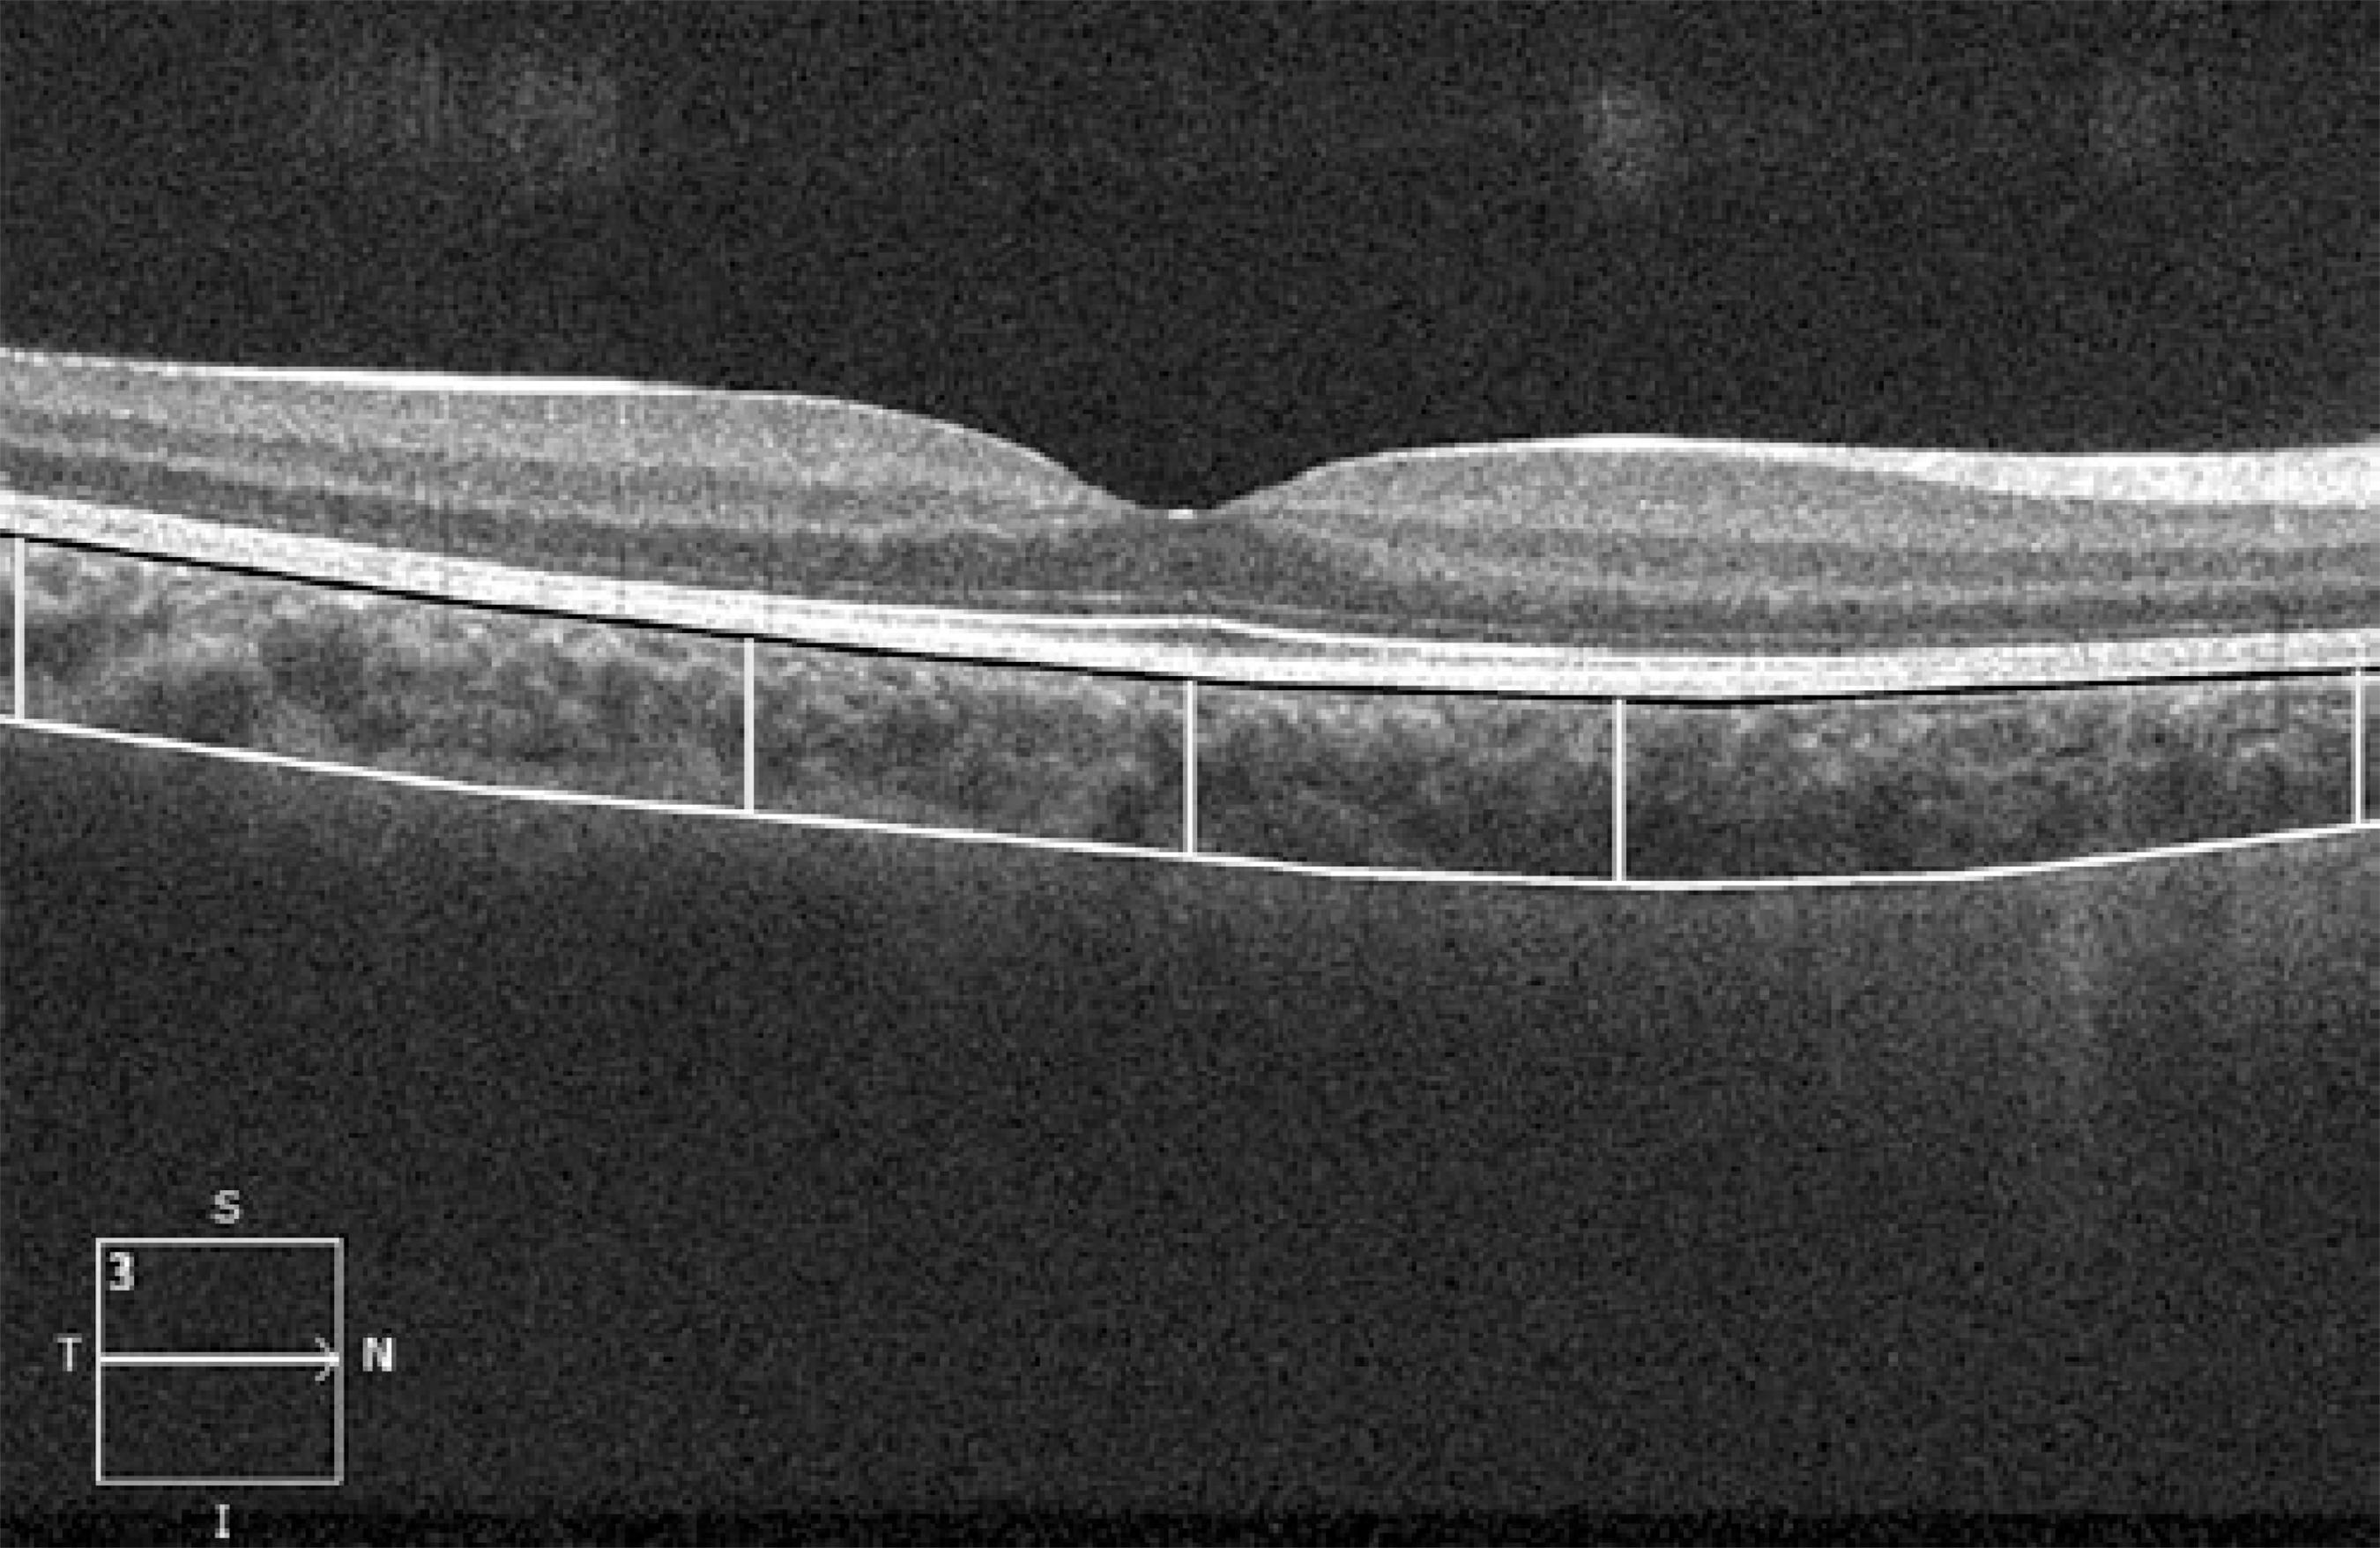

The choroid was visualized by Cirrus HD-OCT with the enhanced depth imaging system (EDI) according to a previously described method. ( 16 )The choroid was imaged by positioning an OCT camera close enough to the eye to obtain an inverted image. Using the Cirrus linear measurement tool, 1 experienced examiner measured CT thickness perpendicularly from the outer edge of the hyper-reflective RPE to the inner sclera at 1000 µm intervals temporal and nasal to the fovea, up to 3000 µm (temporal and nasal CT, respectively; Figure 1). The same examiner performed 2 additional measurements and the average of the 3 measurements was used for the statistical analyses.

Figure 1 A representative Cirrus HD-OCT image. The lines show choroidal thickness measurements retrieved perpendicularly from the outer edge of the hyper-reflective retinal pigment epithelium (black line) to the border with the sclera (white line). Choroidal thickness was measured at 5 points, the subfoveal area, and points 1 and 3 mm temporal and nasal to the fovea (yellow lines).